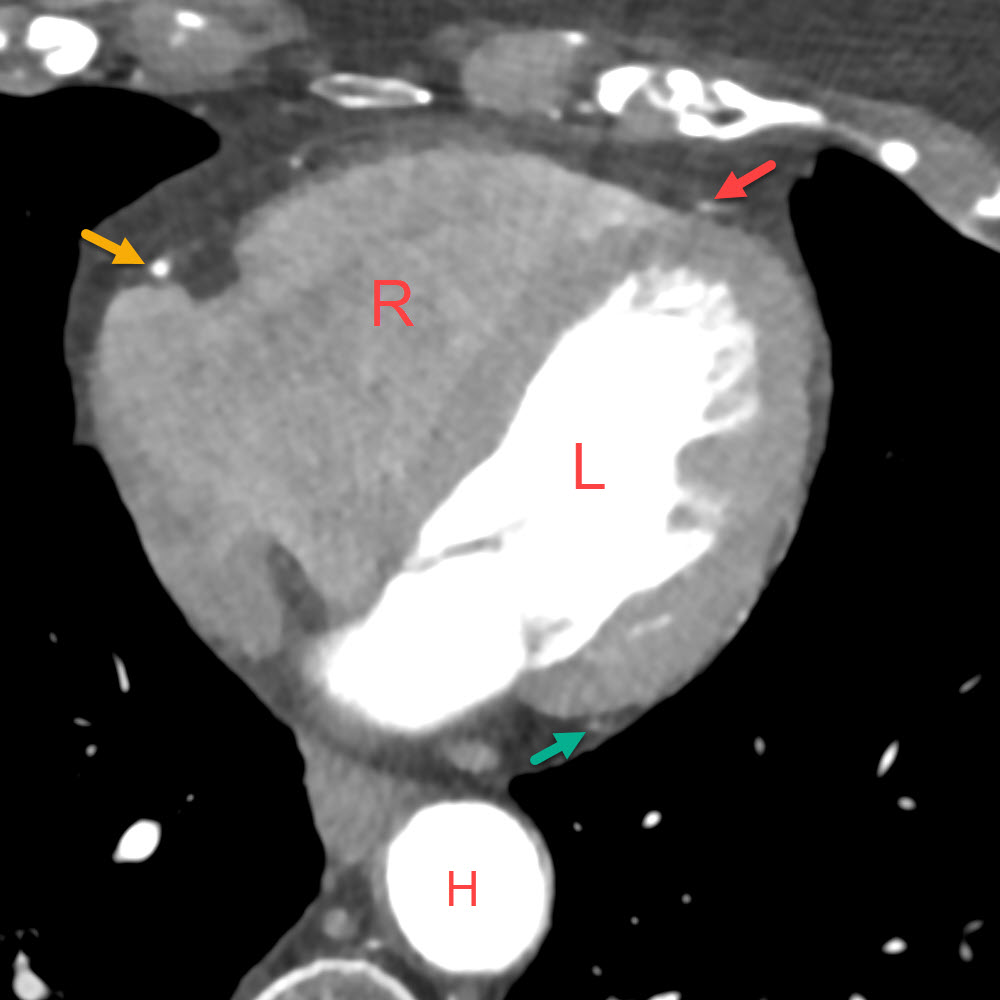

Optional können genaue anatomische Untersuchungen der Herzkranzgefässe durchgeführt werden

CT nach KM-Injektion

Erfassung der Herz-Anatomie:

- R = rechte Herzkammer

- L = linke Herzkammer

- H = Hauptschlagader (Aorta)

- gelb – rechte Herzkranzarterie

- rot – vorderer Ast der linken Kranzarterie

- grün – seitlicher Ast der linken Kranzarterie